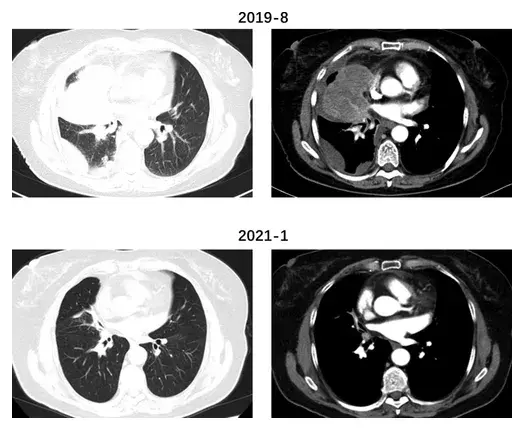

图注:卡瑞利珠单抗+阿帕替尼治疗前后胸部CT检查

2个周期治疗后,患者全身状况明显好转,影像学疗效评估证实部分缓解(PR)。

2021年1月,胸部CT显示,原右肺中叶肿瘤已几乎完全消失,双腋窝、纵隔、肺门多发淋巴结均明显缩小。

免疫组化显示MLH -1(+)、MSH-2(+)、MSH-6(+)、PMS-2(+),提示DNA错配修复(MMR)功能正常。术后2个月,胸部CT显示肺内病变略有增大,因此于2021年5月重新使用卡瑞利珠单抗和阿帕替尼治疗,原发肺癌至今为止仍保持稳定。